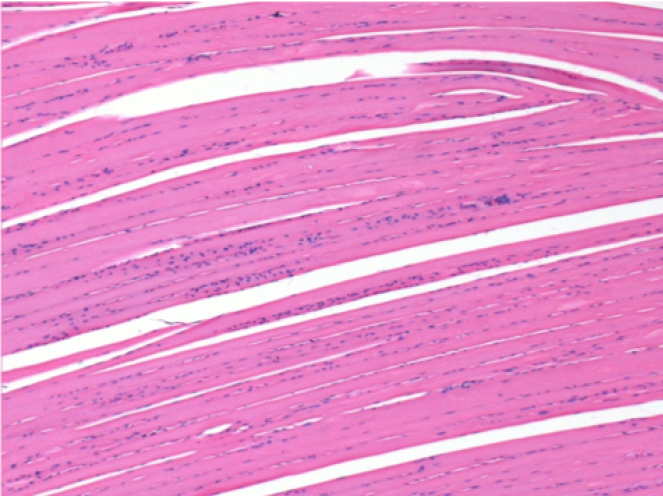

Коментар: Нічого декларувати після введення фізіологічного розчину

Л: Претибіальний м'яз - без лікування